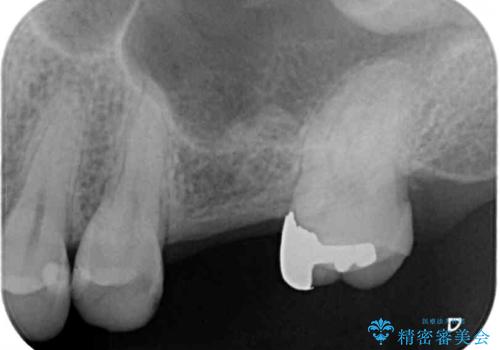

- 深い咬み合わせと前歯のデコボコ、奥歯の欠損を気にして来院された患者様です。

歯列矯正はインビザラインを使用し、矯正治療中の適切な時期に奥歯の欠損部位にインプラントを埋入することとしました。